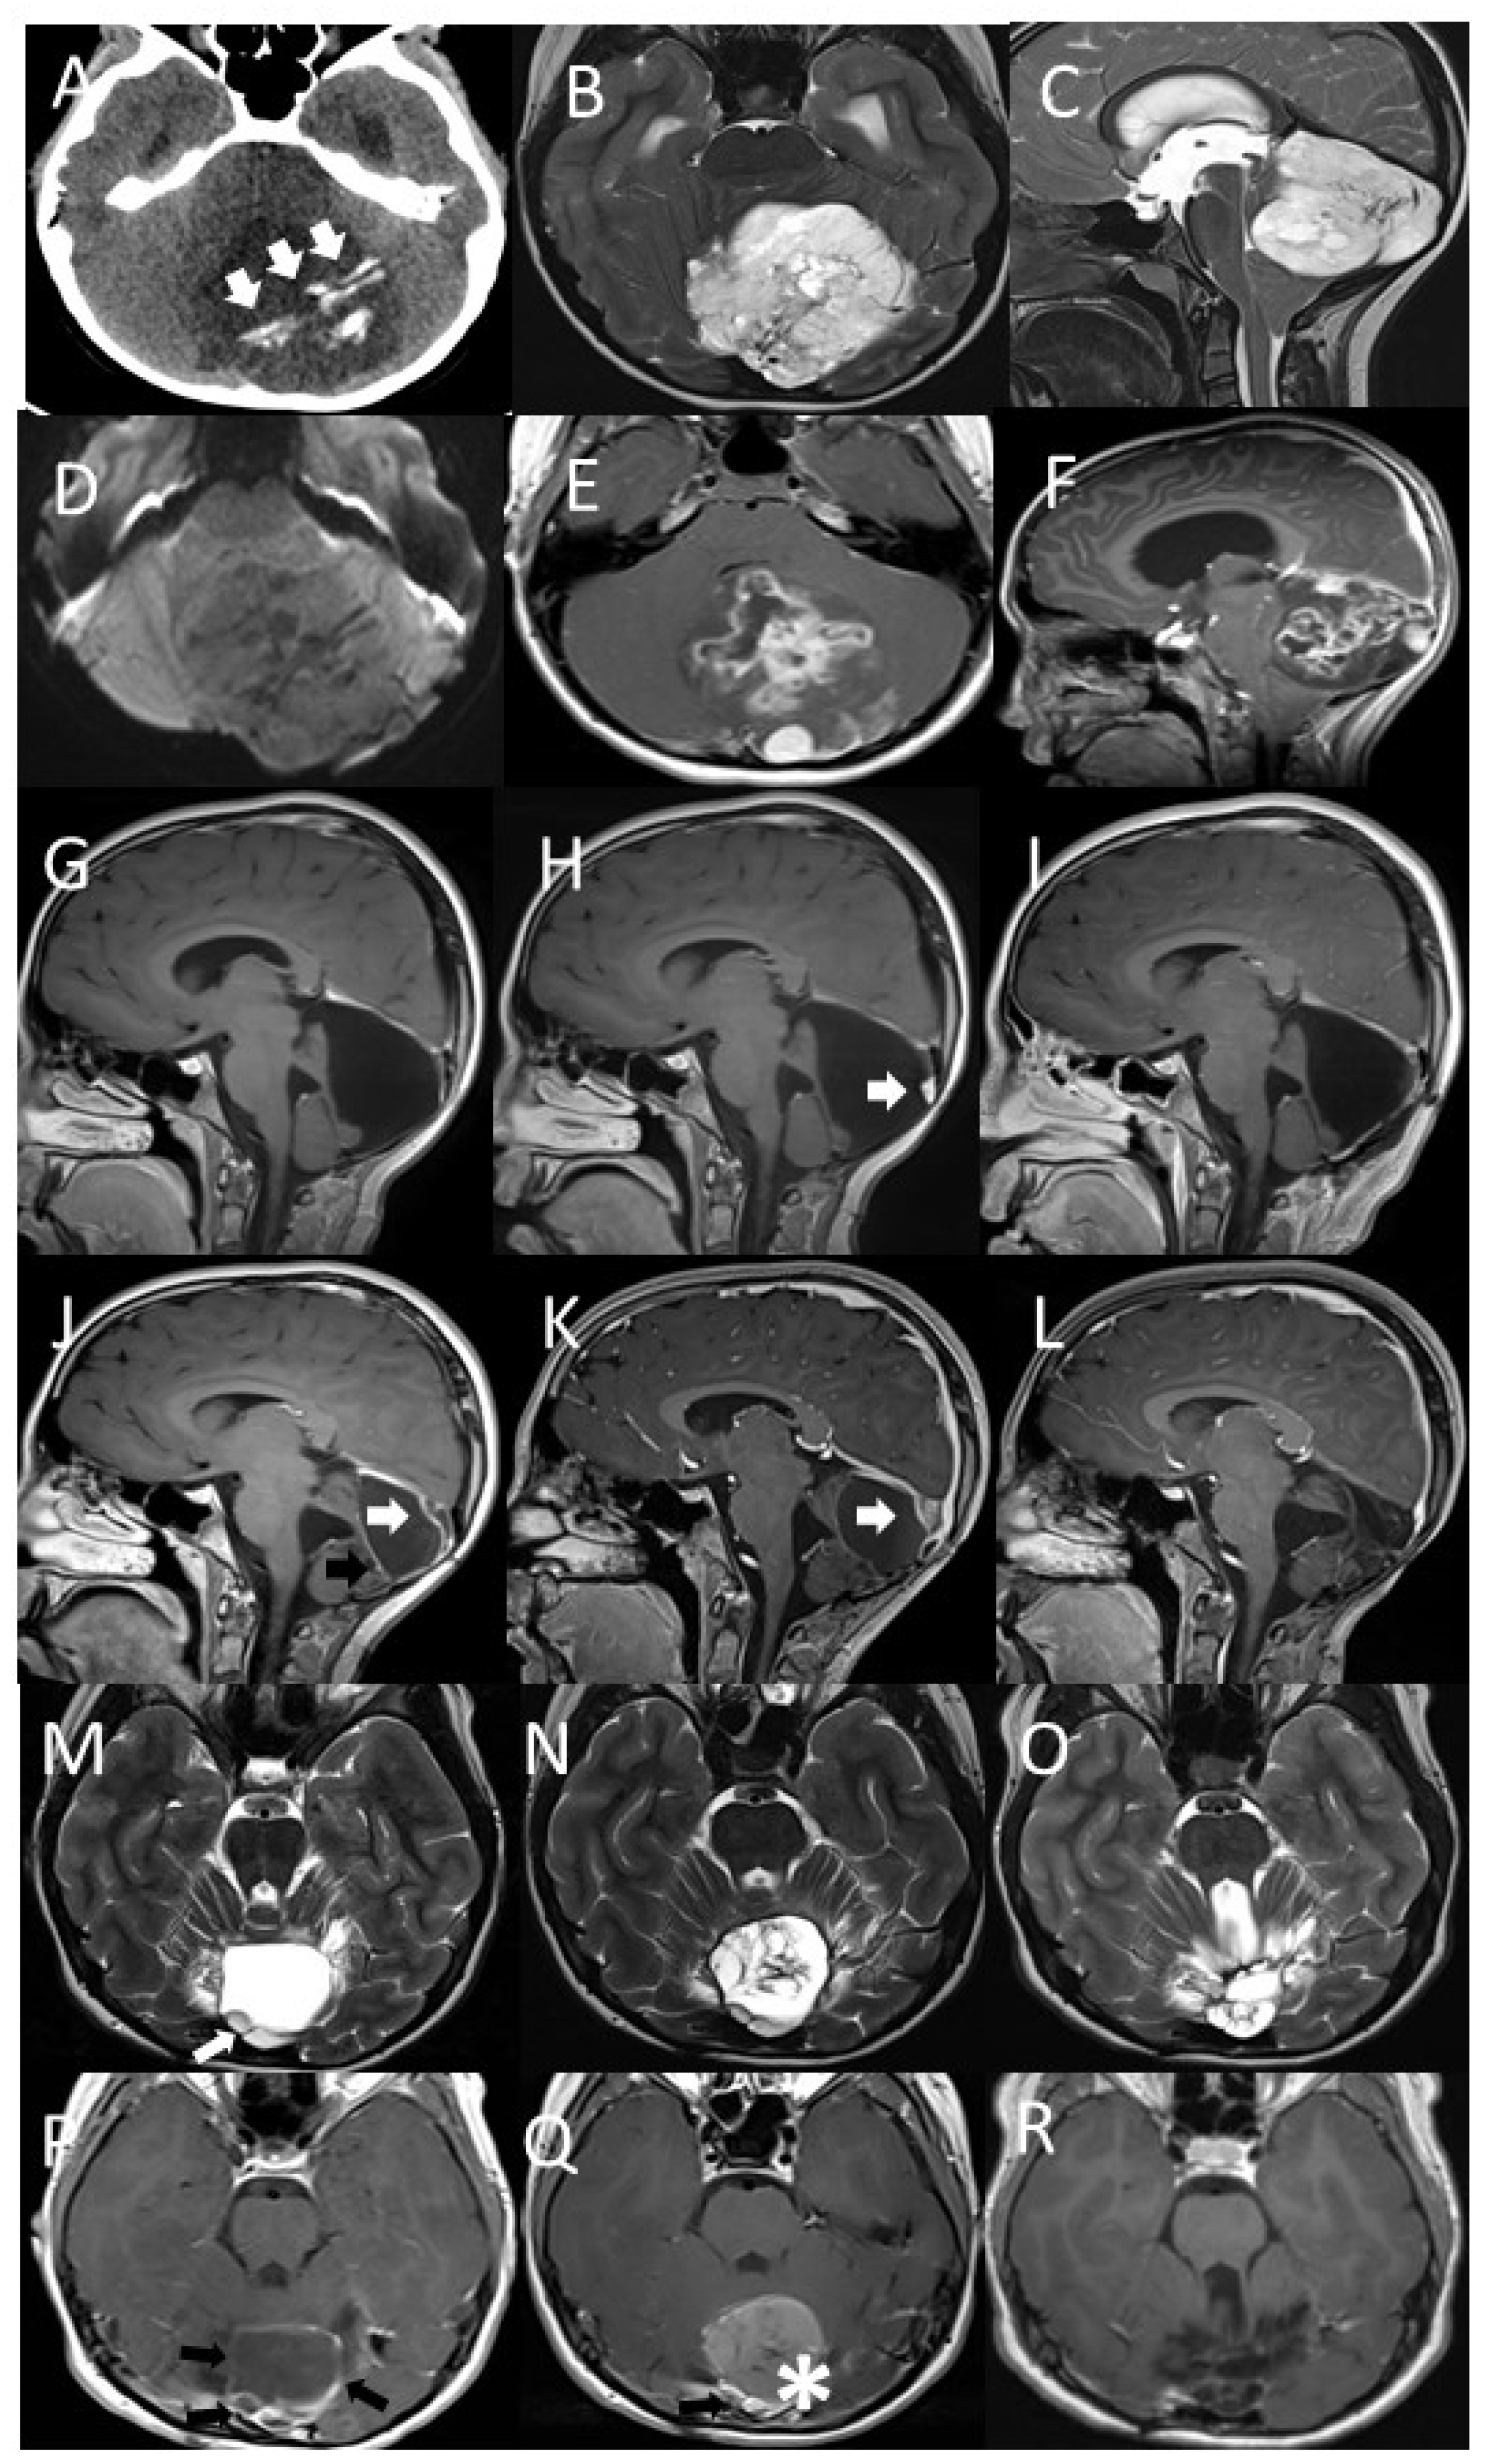

A nine-year-old girl was referred to the Pediatric Emergency Department for worsening headache episodes that began about a year previously associated with vomiting. Clinical evaluation showed she had no neurological abnormalities. Ophthalmological evaluation was then performed with the finding of signs of intracranial hypertension. Urgent brain computed tomography (TC) was performed, showing the presence of obstructive triventricular hydrocephalus caused by a voluminous median expansive cerebellar lesion (Figure 1A). Brain and spinal magnetic resonance imaging (MRI) confirmed the presence of an intra-axial vermian lesion that came to lick the cistern of the quadrigeminal lamina (Figure 1B–F).

Figure 1.

Axial CT image (A), axial (B), and sagittal (C) T2w MRI images show a well-demarcated cerebellar mass, compressing fourth ventricle, with intratumoral mineralization (arrows), elevated diffusion coefficient (C) indicating low cellularity. Axial (D) and sagittal (E) Gd T1w images show inhomogeneous contrast enhancement. Sagittal Gd T1w images show complete tumor excision (G), parietal nodule of the surgical cavity with contrast-enhancement in relation to disease recurrence (H, arrow), completely removed at second surgery (I). Sagittal Gd T1w images show new relapse of pathology (J) with marginal contrast-enhancement of the surgical cavity (black arrow) and peripheral nodular aspects (white arrow); the latter slightly increased at early post-proton therapy control (K, white arrow). The last follow-up shows complete disappearance of these pathological findings (L). Axial T2w (M,N,O) and GdT1w (P,Q,F) images show new relapse of pathology with peripheral nodular aspects (M, white arrow) and marginal contrast-enhancement of the surgical cavity (P, black arrows). Early post-proton therapy follow-up shows slight increased contrast-enhancement (Q, Black arrow) along with hemorrhagic distension of the surgical cavity (Q, star). The last follow-up shows complete disappearance of these pathological findings and tissue distortion with foci of malacia (R).

The patient was then urgently subjected to endoscopic third ventriculocisternostomy neurosurgery with clear improvement of the intracranial hypertension and resolution of headaches and emesis. A few days later, the girl underwent suboccipital craniotomy surgery with macroscopically complete removal of the lesion. The post-operative course took place in the absence of significant complications. A brain MRI performed twenty-four hours after surgery documented the complete removal of the mass (Figure 1G).

Two years after diagnosis, a nodular lesion in the surgical field was discovered on a follow-up MRI (Figure 1H). The patient therefore underwent a second neurosurgery with complete removal of the mass from a macroscopic point of view (Figure 1I). Histological analysis confirmed the recurrence of the same neoplasm (Figure 2D–F).

Eight months after the second surgery, an MRI documented a second recurrence at the local level (Figure 1L). The girl was therefore a candidate for proton therapy program (Figure 1M). The proton treatment was carried-out for one month (Figure 3A–C). Dose distributions of the 3-fields proton plan, optimized with single-field-optimization (SFO) technique to deliver 54 Gy relative biological effectiveness (RBE) in 30 fractions (1.8 Gy RBE per fraction).

Three years after the end of proton therapy, the patient has no evidence of further disease recurrence during the MRI performed at follow-up (Figure 1N).